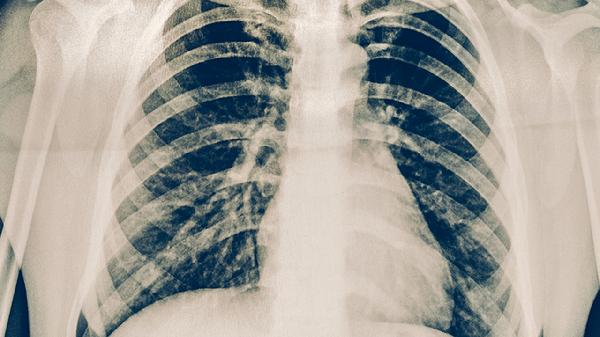

肺結核的常見發(fā)病癥狀主要有咳嗽、咳痰、咯血、胸痛、發(fā)熱等。肺結核是由結核分枝桿菌感染引起的慢性傳染病,早期癥狀可能不明顯,隨著病情進展癥狀會逐漸加重。

肺結核患者最常見的癥狀是咳嗽,早期多為干咳,隨著病情發(fā)展可出現咳痰??人猿掷m(xù)時間較長,一般超過2周,且常規(guī)止咳藥物治療效果不佳。咳嗽可能與結核分枝桿菌感染導致肺部組織炎癥反應有關?;颊呖勺襻t(yī)囑使用異煙肼片、利福平膠囊、吡嗪酰胺片等抗結核藥物進行治療。

肺結核患者咳出的痰液多為白色黏液痰,合并感染時可變?yōu)辄S色膿性痰。部分患者痰中可帶血絲,嚴重者可出現大量咯血??忍蛋Y狀與肺部結核病灶破壞支氣管黏膜有關。患者需注意保持呼吸道通暢,避免痰液堵塞氣道。

約三分之一的肺結核患者會出現咯血癥狀,輕者為痰中帶血,重者可出現大咯血??┭怯捎诮Y核病變侵蝕肺部血管所致。出現咯血癥狀時,患者應立即臥床休息,避免劇烈活動,并及時就醫(yī)治療。醫(yī)生可能會使用止血敏注射液、氨甲環(huán)酸片等止血藥物。

肺結核患者可能出現胸部隱痛或刺痛,深呼吸或咳嗽時疼痛加重。胸痛多因結核病變累及胸膜引起胸膜炎所致?;颊呖勺襻t(yī)囑使用對乙酰氨基酚片緩解疼痛,同時需配合抗結核治療。胸痛持續(xù)不緩解或加重時應及時就醫(yī)。

肺結核患者常出現午后低熱,體溫多在37.5-38.5℃之間,可伴有盜汗、乏力等癥狀。發(fā)熱是機體對結核分枝桿菌感染產生的免疫反應?;颊邞⒁庑菹ⅲ囡嬎?,保持室內空氣流通。醫(yī)生可能會建議使用乙胺丁醇片等抗結核藥物進行治療。